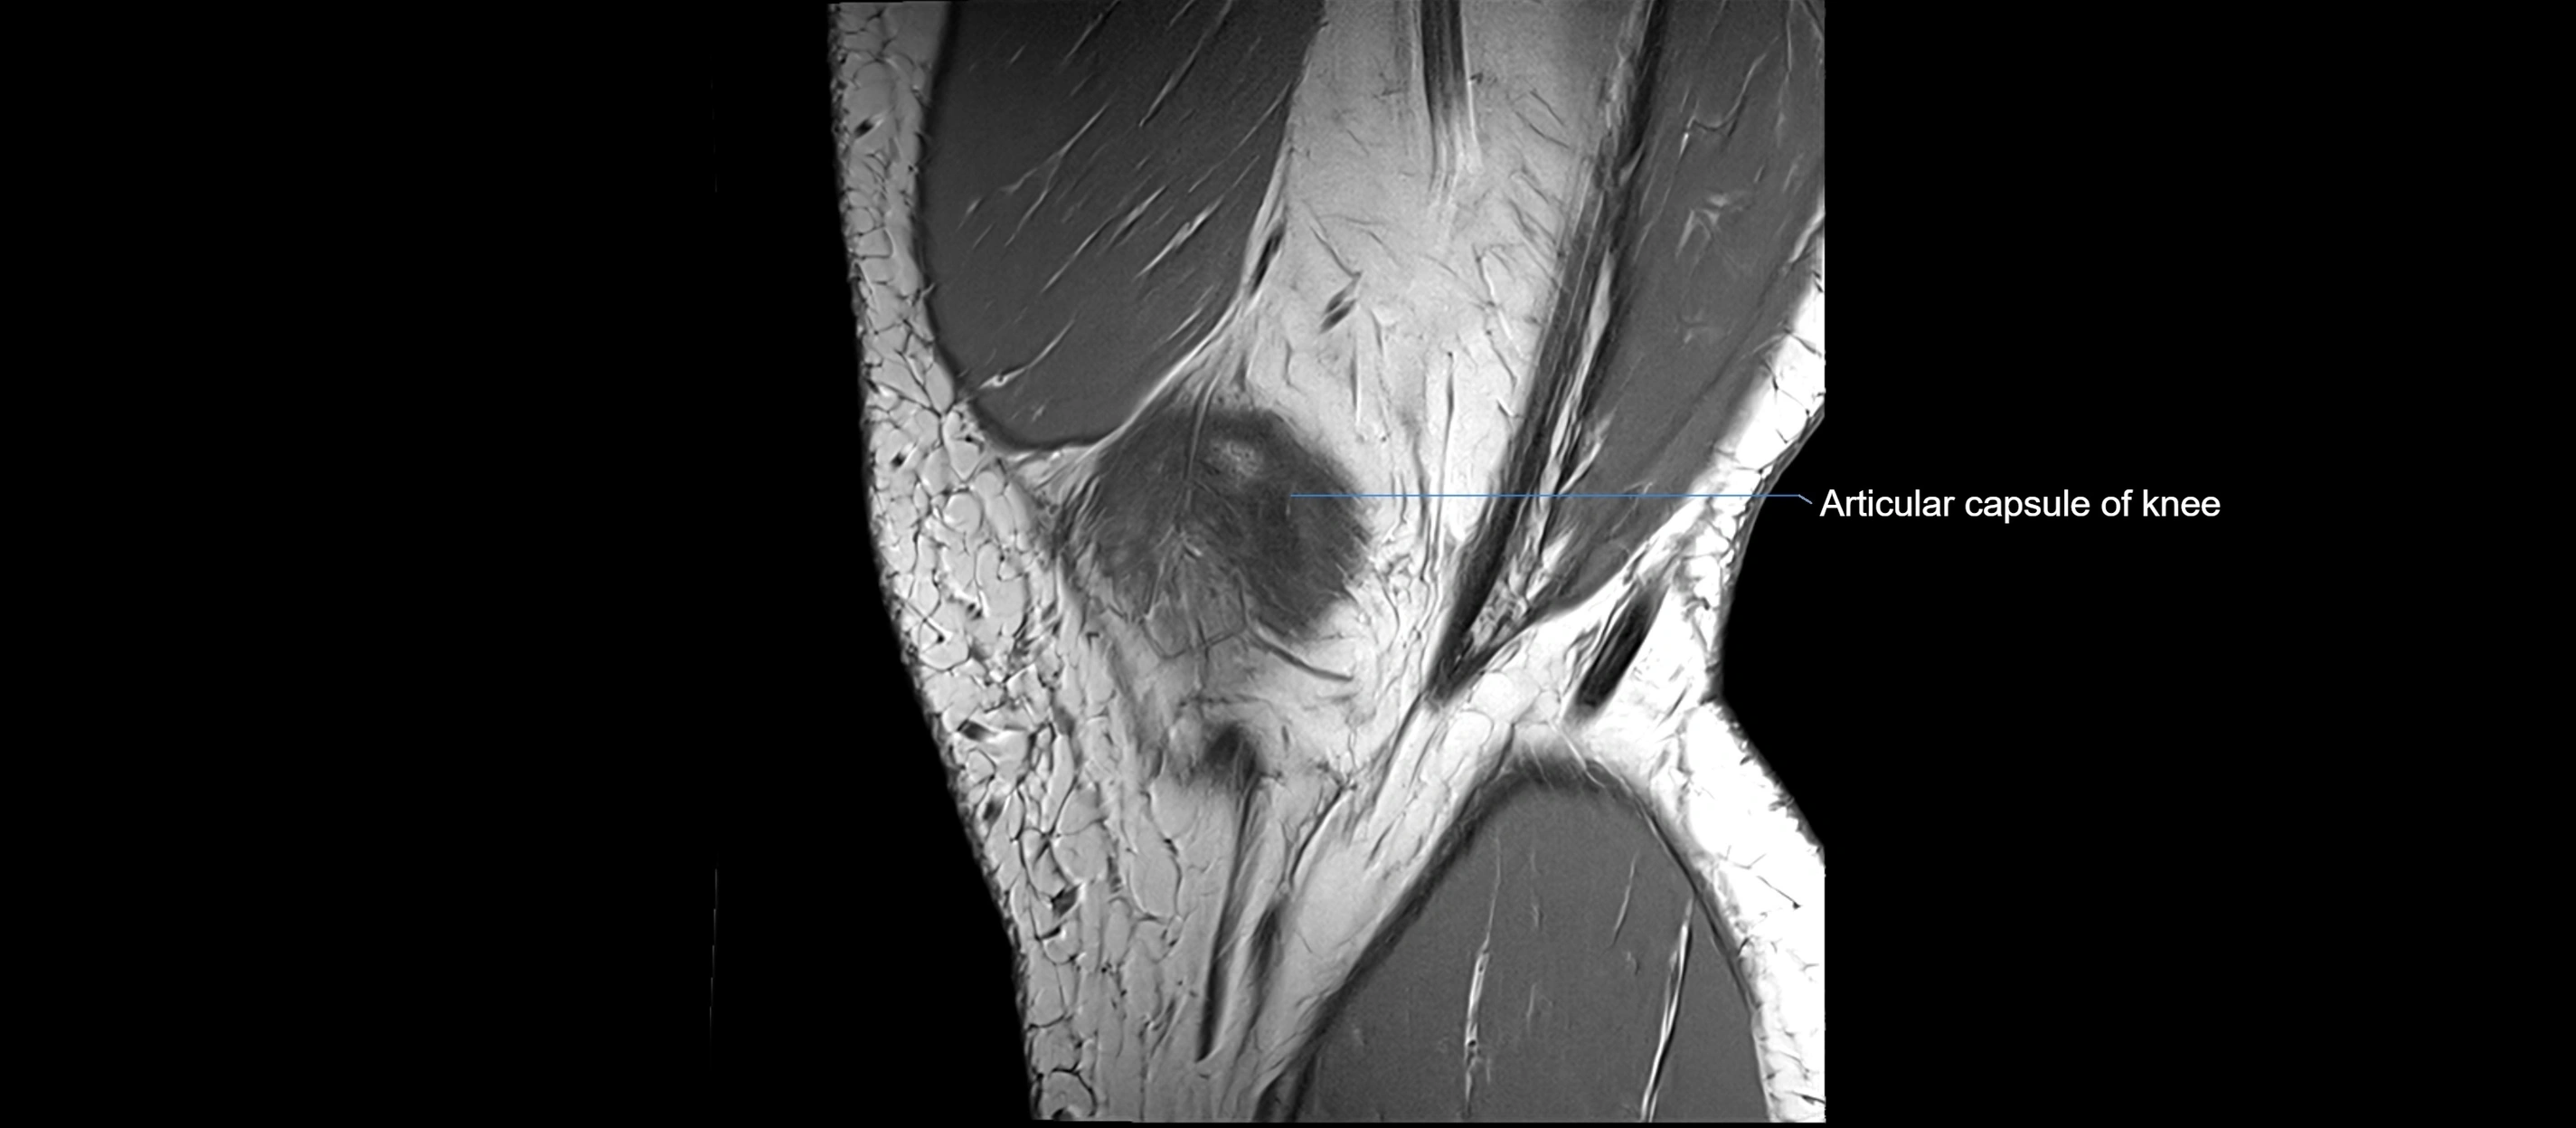

MRI images

image